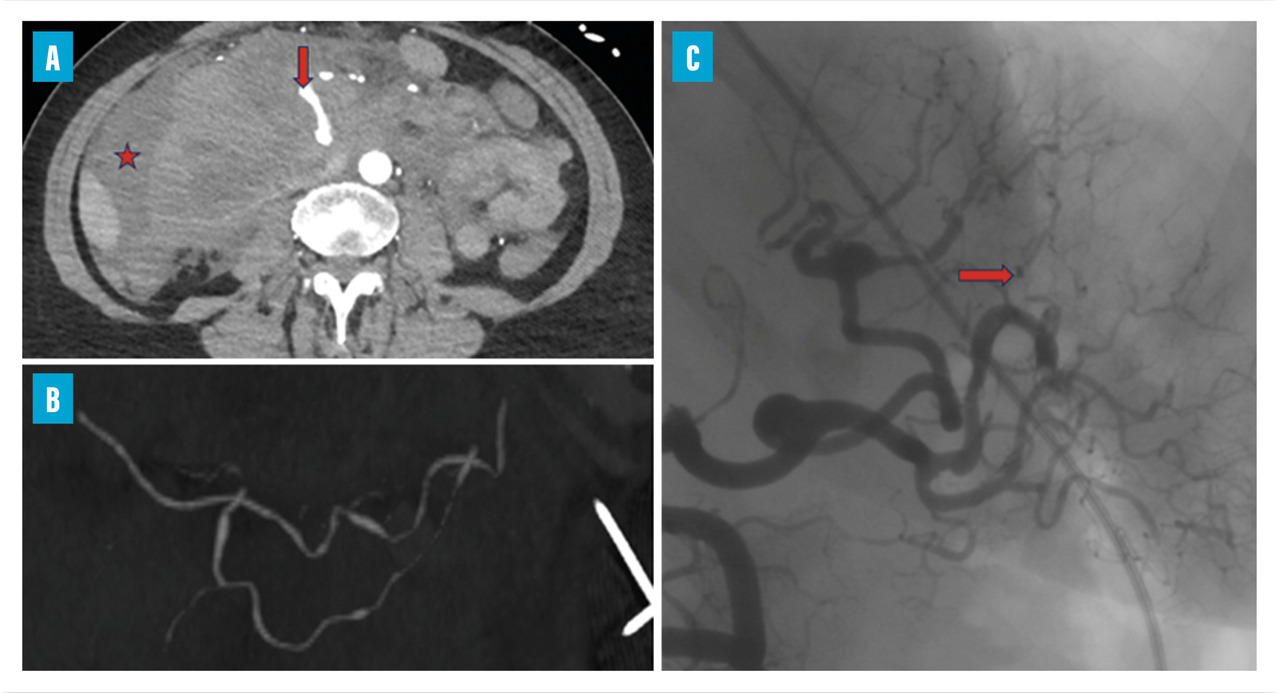

Les atteintes digestives et rénales sont vasculaires, en lien avec des sténoses des moyens vaisseaux, responsables de phénomènes ischémiques et/ou de microanévrismes (fig. 4).6 Leur diagnostic se confirme à l’imagerie, notamment par une angiotomodensitométrie (TDM). L’artériographie, examen de référence, peut s’avérer nécessaire, à visée diagnostique en cas de négativité de la TDM,2 mais surtout à visée thérapeutique, permettant une artério-embolisation en cas d’hémorragie grave.

Les douleurs abdominales, volontiers post-prandiales, sont fréquentes. Elles peuvent être révélatrices de complications sévères telles que les perforations digestives ou les hémorragies intrapéritonéales (fig. 5), gastro-intestinales ou sous-capsulaires. Ces complications s’observent chez 4 % des patients, de même que les cholécystites et pancréatites alithiasiques. Au total, jusqu’à 14 % des patients atteints de PAN peuvent subir un geste chirurgical pour une complication digestive.5,15

L’atteinte rénale se manifeste soit par une hypertension artérielle isolée, parfois sévère, soit par une authentique néphropathie vasculaire (insuffisance rénale aiguë, protéinurie tubulaire +/- hématurie microscopique, stigmates biologiques de microangiopathie thrombotique).16 Elle est en lien avec des sténoses, pouvant aussi entraîner des infarctus rénaux. Les microanévrismes des artères rénales et de leurs branches peuvent être responsables d’hématomes sous-capsulaires ou rétropéritonéaux.17 Si l’insuffisance rénale ne se voit que dans 12 % des PAN,5,6 cette néphropathie vasculaire, non glomérulaire, représente un enjeu diagnostique majeur. Contrairement aux autres vascularites, notamment celles ­associées aux anticorps anticytoplasme des polynucléaires neutrophiles (antineutrophil cyto­plasmic antibodies [ANCA]), la biopsie rénale ne doit pas être réalisée avant d’avoir exclu les microanévrismes en artériographie, au ris­que de complications hémorragiques.16,18

Imagerie artérielle non invasive en première intention

L’imagerie artérielle peut suffire à poser le diagnostic, en cas de suspicion clinique et de présence d’anévrismes sacciformes ou fusiformes, de sténoses des artères de moyen calibre, notamment rénales, hépatiques ou digestives.2,4 En première intention, une imagerie non invasive telle que l’angio-TDM ou l’angio-­IRM (en cas de contre-indication aux produits de contraste iodés) est recommandée mais nécessite un regard exercé de la part du radiologue. L’artériographie reste l’examen de référence en cas de doute diagnostique, mais n’est réalisée qu’en deuxième intention, compte tenu d’éventuelles complications, à type d’hématome, de faux anévrismes au point de ponction ou de néphropathie aux produits de contraste.2 Elle peut aussi jouer un rôle thérapeutique, en cas de saignement sévère, permettant de réaliser une embolisation.